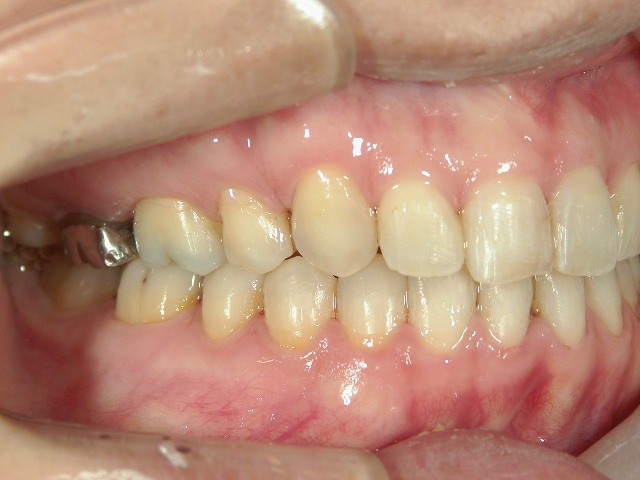

矯正歯科 治療前

矯正歯科(全顎ワイヤー矯正)治療後

全顎ワイヤー矯正 症例(2)

36歳女性 磐田市

在住

治療期間2年6

ヶ月